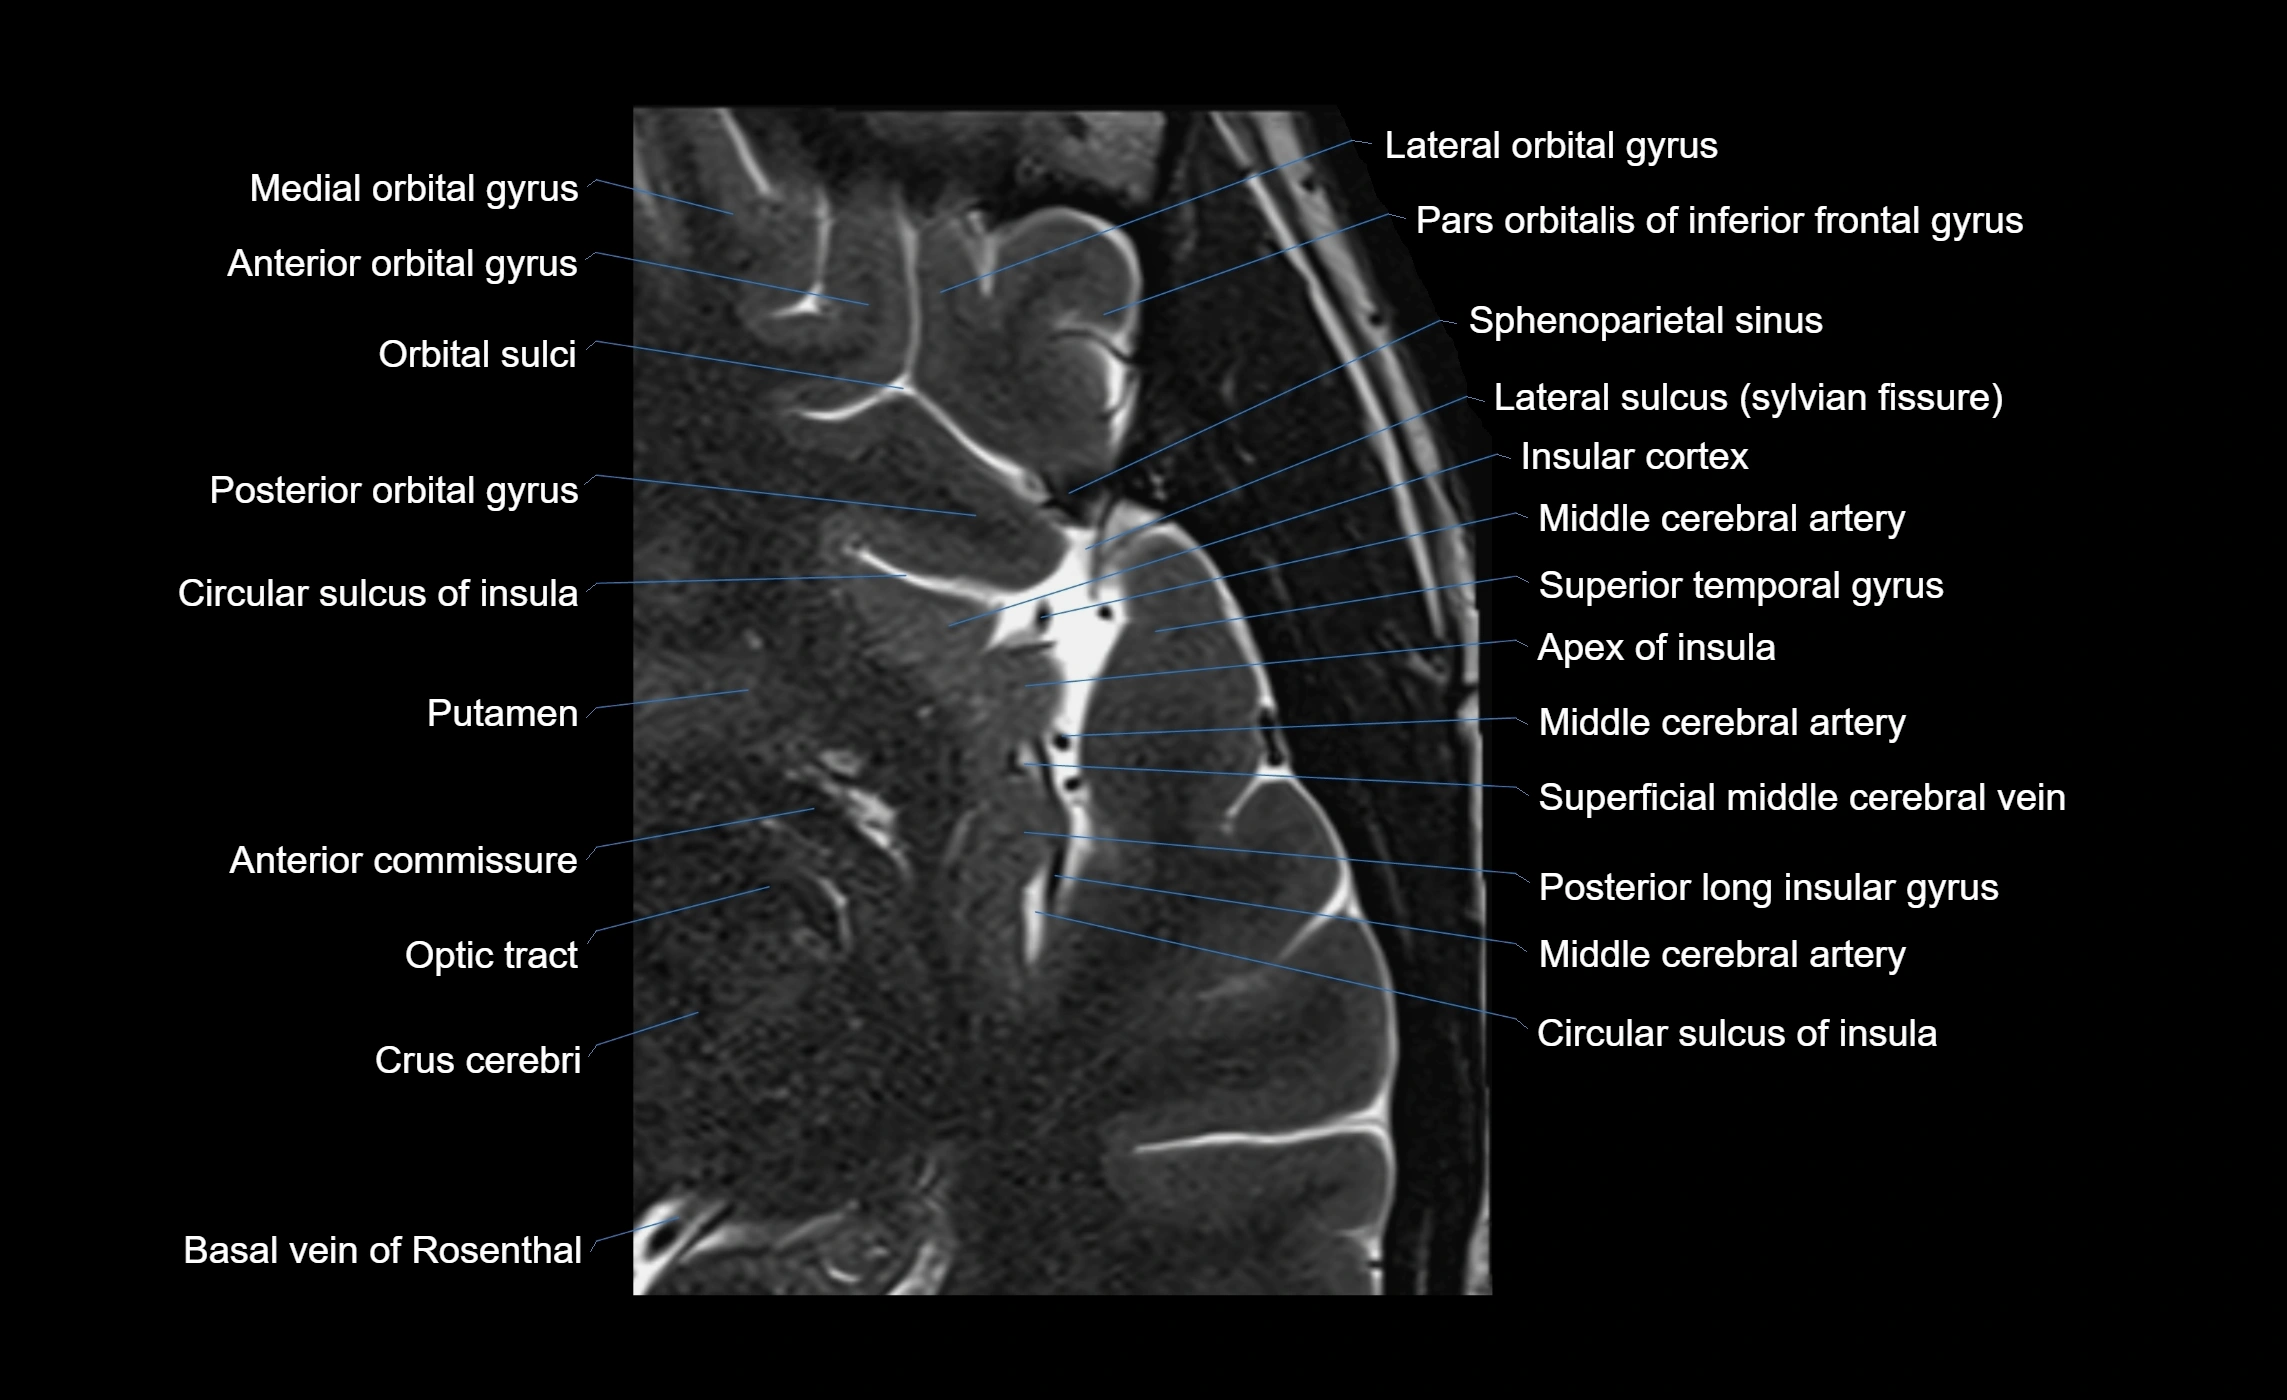

The anterior ascending ramus of the Sylvian fissure is a significant anatomical landmark in the lateral surface of the cerebral hemisphere. It represents one of the key branches of the Sylvian fissure (also known as the lateral sulcus) and plays an essential role in demarcating the boundaries between important cortical regions, notably within the frontal and parietal lobes. Understanding its anatomy and imaging appearance is crucial in neuroradiology, neurosurgery, and neuroanatomy for accurate localization and identification of adjacent brain structures.

• The anterior ascending ramus is a short, superiorly oriented branch that arises from the main stem of the Sylvian fissure.

• It projects upward (anteriorly and slightly dorsally) from the lateral sulcus into the inferior frontal gyrus.

• This ramus separates the pars opercularis (opercular part) from the pars triangularis (triangular part) of the inferior frontal gyrus.

• The anterior ascending ramus marks the boundary between Broca's area and adjacent cortical areas in the dominant hemisphere.

• T1-weighted imaging:

• The Sylvian fissure and its anterior ascending ramus appear as low-signal intensity (dark) CSF-filled clefts between the gyri.

• Clear demarcation between adjacent gray and white matter.

• T2-weighted imaging:

• The fissure, including the anterior ascending ramus, is hyperintense (bright) due to CSF signal.

• Better visualization of the separation between opercular and triangular parts of the inferior frontal gyrus.